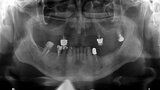

Fig. 29: OPG prior to treatment.

Fig. 30: OPG after placing implants.

Fig. 31: OPG after exposing implants at the lateral section and having used a temporary prosthesis based on telescopes.

Fig. 32: OPG after treatment.